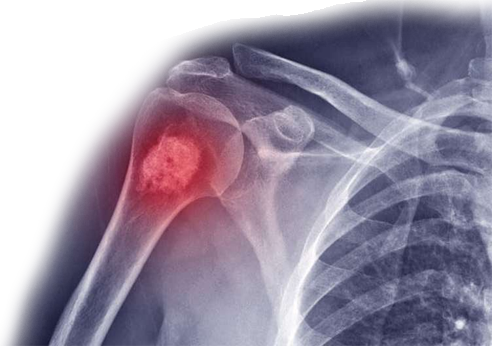

مركز أورام العظام والأورام

سواء كان الورم العظمي ”حميداً“ أو ”خبيثاً“، فإننا نقدم علاجات مصممة خصيصاً لمرضانا.

أنواع الأورام التي يتم علاجها;

أورام العظام الخبيثة:

- الساركوما العظمية

- ساركوما إيوينغ

- الساركوما الغضروفية

علاج مبتكر لإنقاذ الأطراف